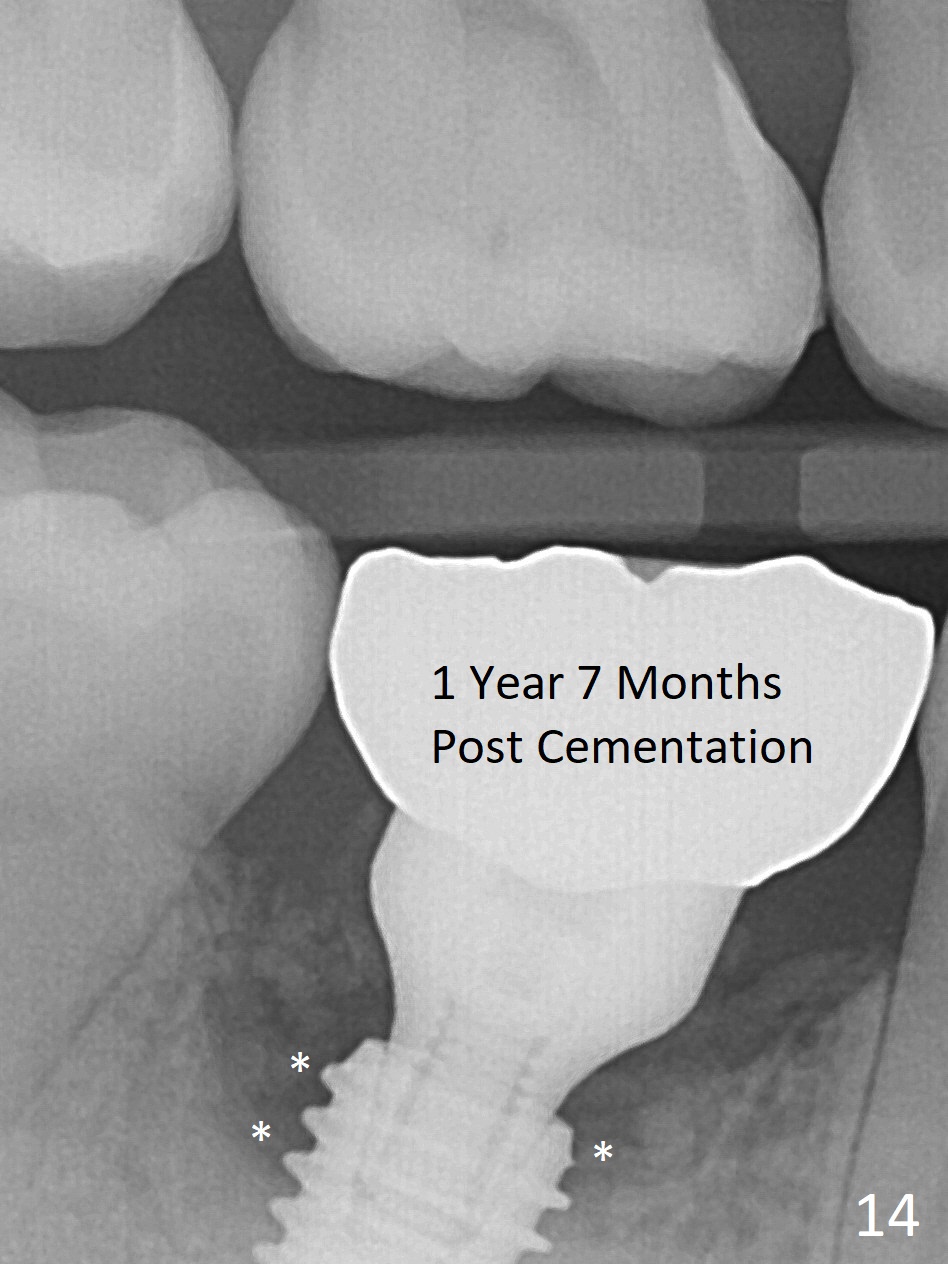

Fortunately no paresthesia is reported postop. Why is the Inferior Alveolar Canal not violated? Fig.7 is a coronal section of CBCT taken for a 40-year-old man at the lower 1st molar (at the septum). At the region, the Canal (brown circle) is close to the lingual plate (L). Because of severe bone loss of the lingual plate of this case (Fig.8 *), osteotomy is intentionally created buccal (green). The deep osteotomy may not contact the Canal, while the hemorrhage may stem from the medullary space (M in Fig.4,7). Bone morphology at the coronal end of the implant apparently changes 4 months postop, suggesting osteointegration (Fig.9). Impression is taken. Bone density around the implant at the crest seems to increase (Fig.10), while there is no soft tissue deficiency 10 months post cementation (Fig.11). The bone appears to regenerate toward the abutment, particularly distally, 14.5 months post cementation (Fig.12). Periimplantitis develops (bleeding on water pik and erythematous and tender buccal gingiva) 1 year 7 months post cementation (Fig.13,14). The 1st three threads are exposed (*). Bone graft with PRF and 6-month membrane or Cytoplast will be needed. Pain disappears 3 days of oral antibiotic. The gingiva looks healthy 1 month later when he returns for bone graft (Fig.15). But the lingual gingival cuff is not so healthy when the crown/abutment is removed (Fig.16 <). Bone graft is not done. For those patients with suboptimal oral hygiene, implants should be placed as low as possible, better with guide for precision.